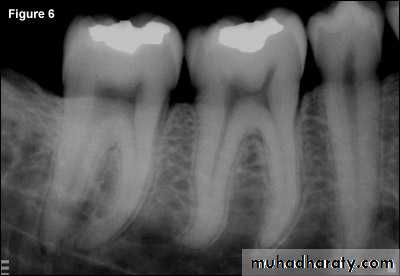

Radiograph of occlusal caries. This radiograph shows (1) severe occlusal caries, which appears as a large radiolucent lesion in the first molar

Bitewing radiograph. This radiograph shows (1) large occlusal caries, (2) radiolucent lines or mach band effect (an optical illusion caused by overlapped enamel), (3) interproximal caries, and

(4) cervical burnout